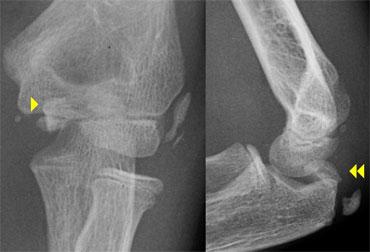

Normal medial epicondyle projecting posteriorly. Notice radial head dislocation and olecranon fracture

Medial Epicondyle avulsion

Mỏm trên lồi cầu trong là một mấu xương vì nó không đóng góp vào sự tăng trưởng theo chiều dọc của xương cánh tay.

Nó nằm ở phía sau của khuỷu tay.

Trên hình chiếu thẳng bên, đặc biệt nếu cánh tay ở tư thế xoay trong, nó có thể chiếu ra phía sau đến mức có thể gợi ý một tổn thương bong điểm bám (hình ảnh).

Tuy nhiên, các tổn thương bong điểm bám thường nằm ở vị trí xa hơn và phía trước hơn.

The radial epiphysis is slipped (arrows). The radiocapitellar line does not pass through the capitellum indicating dislocation and there is a fracture of the olecranon

Gãy cổ xương quay cũng như trật đầu xương quay trong 50% trường hợp có liên quan đến các tổn thương khuỷu tay khác.

Thường gặp nhất là gãy mỏm khuỷu.

Khi đầu xương quay còn rất nhỏ, trượt đầu xương quay có thể bị bỏ sót (hình).